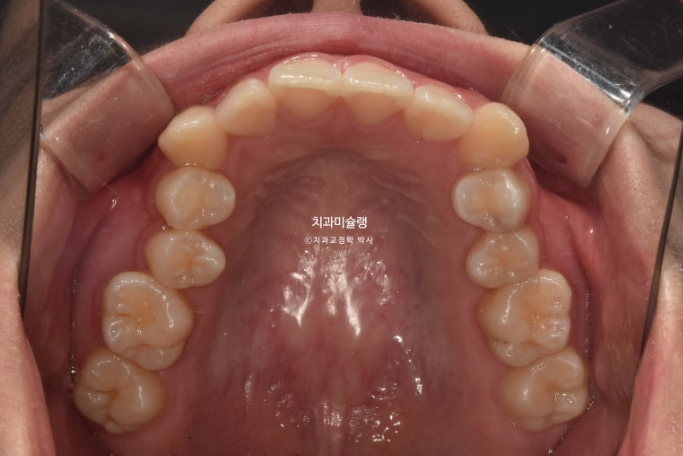

작은어금니 하나가 매복되었다시피 깊게 누워있습니다.

치료계획은 누워있는 덧니를 포함해서 작은어금니 4개 발치

중심선은 잘 맞고 과개교합도 해소가 되었습니다.

어금니 교합은 물샐틈 없는 1급 교합관계 입니다.

치근흡수도 없고 치근평행도는 양호합니다.